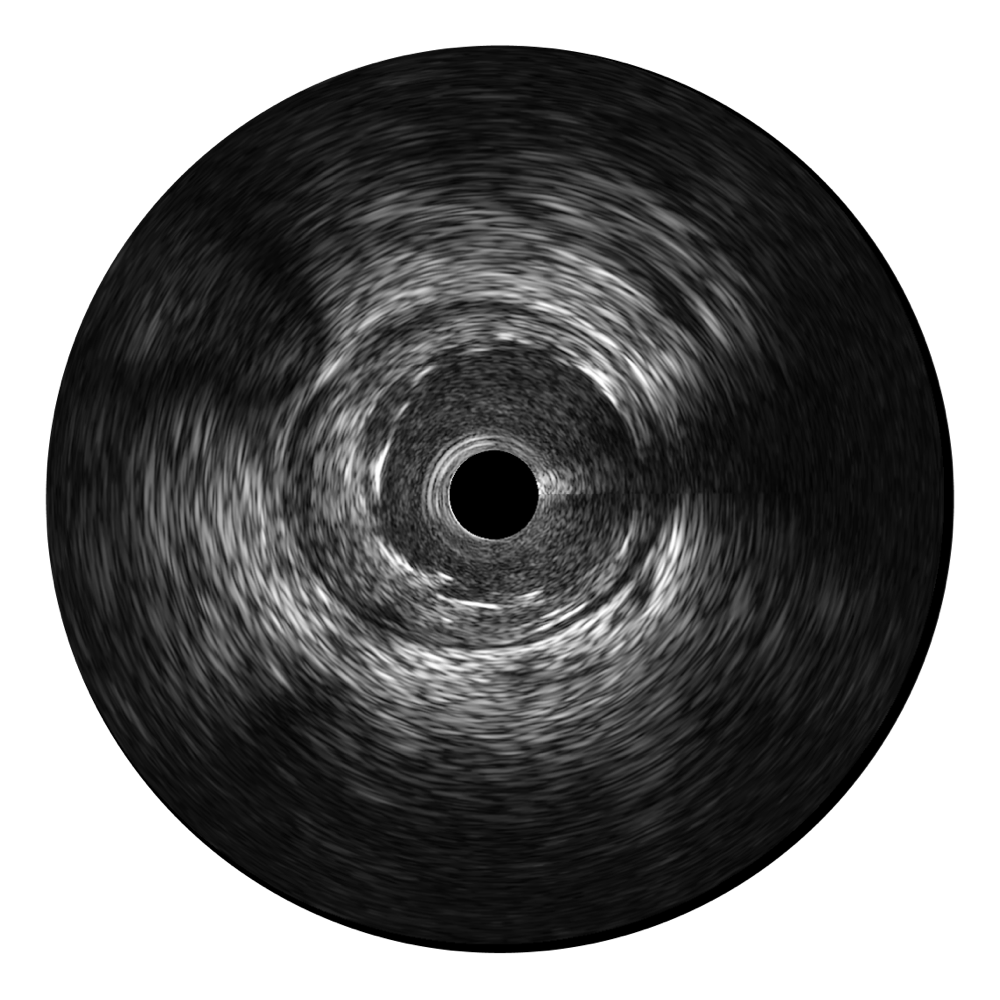

開立寬頻IVUS圖像

對比傳統(tǒng)IVUS導(dǎo)管成像,開立寬頻IVUS圖像的近場支架梁顯影更細(xì)膩,遠(yuǎn)場中膜外血管仍清晰可辨,兼顧遠(yuǎn)中近,兼顧分辨力與穿透深度